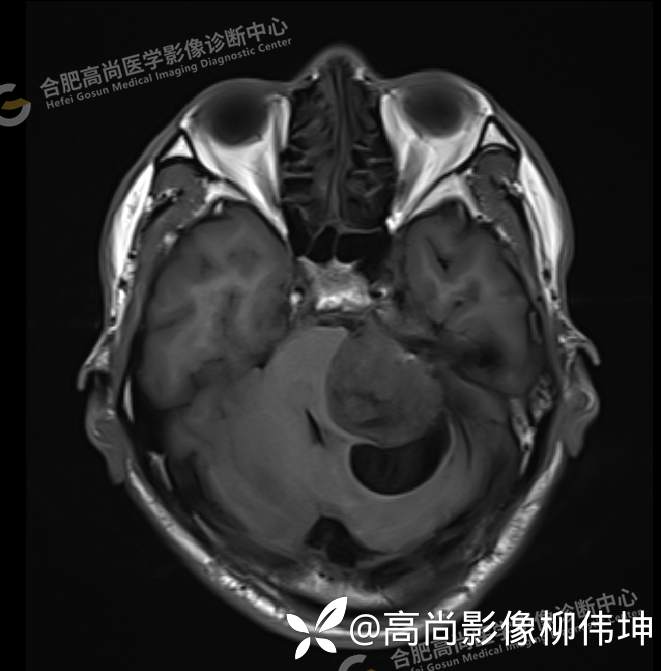

T2WI-tra

颅脑MRI平扫+增强示:双侧大脑半球对称,左侧桥小脑角区可见一团块状异常信号影,边界尚清,病灶与小脑幕宽基底附着呈“D”字征,上缘指状伸入幕缘上生长,病灶大小约43mmx42mmx36mm,其内信号不均,T1WI呈等低信号,T2WI呈混杂等高信号;FLAIR呈高信号,内可见条状低信号影,DWI呈稍高信号,ADC呈低信号,弥散轻度受限,病灶后方左侧小脑半球区可见一大小约33mmx16mm的弧形长T1长T2信号影,FLAIR呈低信号,其周围可见片状高信号影,相邻桥小脑角增宽。脑桥、小脑蚓部,小脑半球、第四脑室、环池受压变形,向右侧偏移,四脑室明显变窄,增强扫描病灶可见不均匀明显强化,邻近脑膜可见线样强化改变。其后方囊性灶未见异常强化。邻近骨质未见明显异常信号。左侧内听道显示正常;左侧中耳乳突内可见不规则性长T1长T2信号影。余脑实质内未见局灶性信号异常。双侧侧脑室及第三脑室体积增大,中线结构居中。矢状面示垂体形态大小正常,未见局灶性异常信号。

1.左侧桥小脑角区占位伴周围囊变,轻度梗阻性脑积水;考虑左小脑幕脑膜瘤。